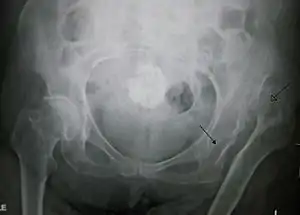

Hip dysplasia diagnosed by ultrasound[40] and projectional radiography ("X-ray").[41] Ultrasound imaging is generally preferred at up to 4 months due to limited ossification of the skeleton.[39][notes 1]

Despite the widespread of ultrasound, pelvis X-ray is still frequently used to diagnose or monitor hip dysplasia or for assessing other congenital conditions or bone tumors.[42] The most useful lines and angles that can be drawn in the pediatric pelvis assessing hip dysplasia are as follows:[42] Different measurements are used in adults.[42]